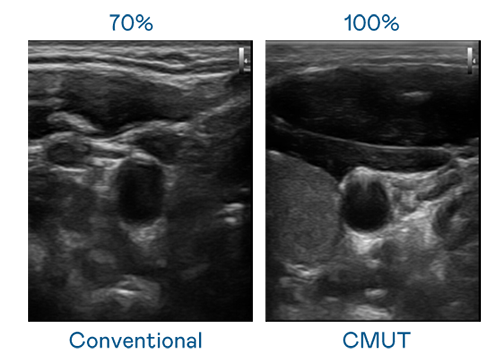

CMUT 技術是一種用電容式微機電元件來產生超音波訊號的技術。與傳統 PZT 壓電式技術相比,CMUT 頻寬增加 30%,更寬頻的超音波訊號讓影像解析度大幅提升,是實現高影像品質醫療超音波掃描、促進精準醫療發展的關鍵技術。

大頻寬帶來超清晰影像

超音波影像的解析度高低,首先取決於探頭能發出的訊號頻寬。918博天娱乐 CMUT 可提供高清晰的超音波訊號,提供高頻寬、高靈敏度、影像紋理細節更高的超音波影像,協助醫護人員縮短影像判讀時間及利用精準的醫療影像進行診斷。